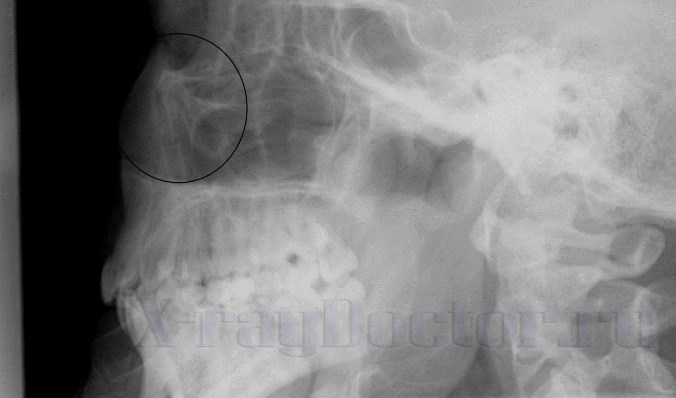

Рентген при определении степени перелома носовых костей выполняется сразу после прямого удара в область лица. Для рентгенодиагностики применяется прямая и боковая проекция, которые позволяют изучить состояние тканей.

Прямая рентгенография показывает только деструкцию со смещением. Для установления стороны повреждения делают снимки носа в левой и правой боковой проекциях. При этом больной вначале укладывается на левую сторону, а затем на правую сторону.

Вторым способом диагностики является рентгенограмма, выполненная в носоподбородочной проекции. На таком снимке четко прослеживаются носовые кости и отростки верхней челюсти. Из-за аксиального хода рентгеновских лучей в данной проекции можно определить смещение отломков при снимках сломанного носа.

Давние повреждения четко прослеживаются на рентгенограмме по выраженной костной мозоли. Свежие переломы определяются лишь по смещению отломков. Для определения импрессионных смещений можно сделать прицельную рентгенографию лобной пазухи, на которой хорошо прослеживаются носовые полости.

Симптом «воздушного пузыря» на рентгенограмме черепа и придаточных пазух носа в прямой проекции наблюдается на рентгеновском снимке при попадании воздуха в лобную часть черепа. Воздушный пузырь на снимке локализуется в области свода и лобных костей.

Характер повреждения значительно зависит от деформации носовой кости, силы удара и области приложения. Для рентгенодиагностики большое значение имеют конструктивные особенности сломанного носа. Если его структура тонкая и короткая, на снимке линия просветления может не определяться (она находится за пределами разрешения).

Особенности переломов носовых костей

Если удар нанесен сбоку, на рентгенограммах можно наблюдать расширение фронтальных костей. Феномен «hock», который наблюдается на снимке в таком случае, довольно убедителен. При нем наблюдается различие в ширине обоих скатов. На снимках в правой и левой боковой проекциях четко прослеживается разница в ширине носовых костей. Механизм образования подобной деформации ясен – возникает трещина носовых костей вблизи основания (у прилегания к глазницам). При пальцевом ощупывании спинки на ней отмечает выступ, образованный деформацией костей.